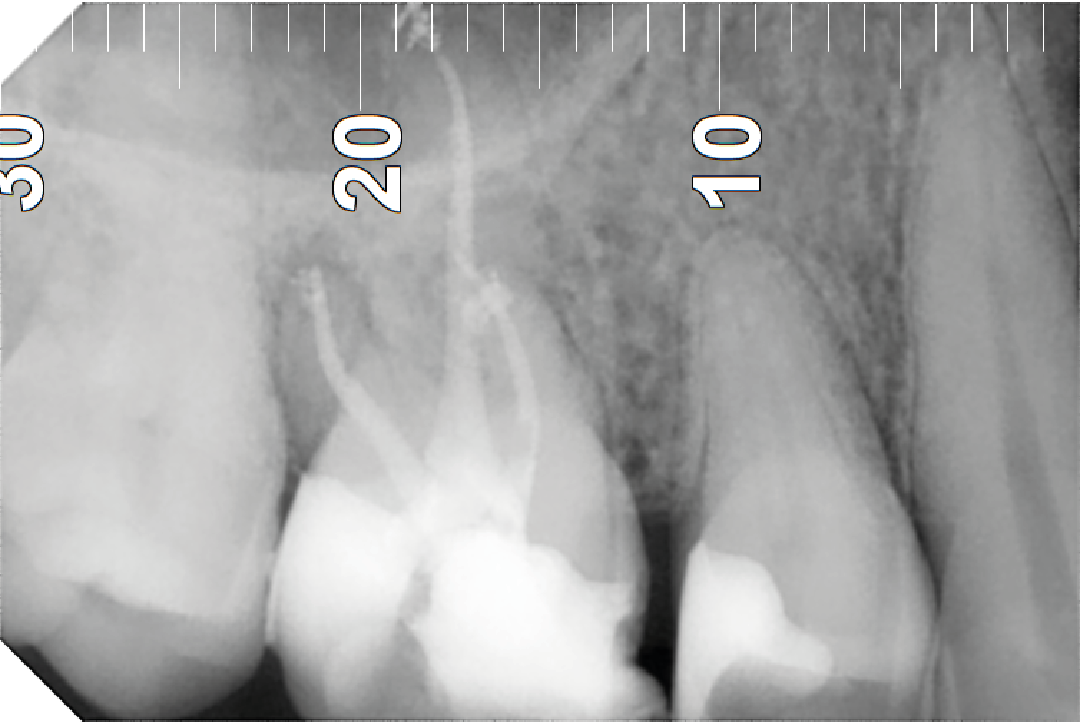

¿Cómo se realiza una endodoncia?

Se realiza con anestesia local y comienza con un aislamiento absoluto, para impedir la contaminación de saliva, limpiamos la cavidad hasta llegar a la cámara pulpar donde ubicamos los conductos radiculares y donde se inicia el proceso de desinfección y limpieza de todas las bacterias, hasta que los rellenamos con un material biocompatible que produce un sellado hermético en la entrada de cada uno.